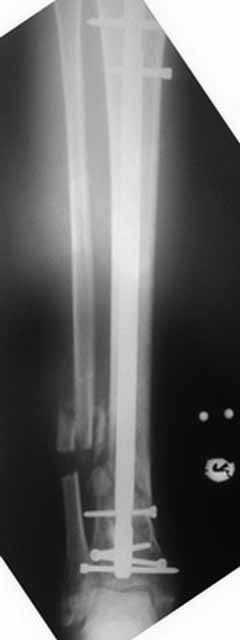

Да уж! Ни один из 3-х оперативных методов предшествующего лечения не был исполнен правильно. Везде был серьезный брак. Хотя любой из методов вполне мог бы и должен был бы привести к сращению,...если бы, да кабы.. В результате имеем то, что имеем. Что делать? Во-первых - подумать. Во-вторых - еще раз подумать. В третьих - еще больше подумать.

Иван, Вам видится зона перелома мертвой, а мне вовсе нет. Есть ли возможность сделать сцинтиграфию с технецием? Это может доказать нежизнеспособность или воспаление концов. Тогда есть резон для такой "крайней" меры как резекция. Есть ли клинические признаки инфекции в области первичной раны?, п\операционных рубцов?, в местах проведения спиц (нет ли спицевого остеомиелита)?.. В общем, вопросов может быть много.

Если нет данных за инфекцию в зоне перелома мы бы аппараптом дозированно устранили деформацию и, не удаляя дистальный фрагмент сломанного гвоздя, закрыто, после рассверливания заштифтовали бы достаточно толстым и надлежащей длины гвоздем.... Если есть спицевой остеомиелит, то также сначала аппарат, затем рассверливанме и цементный спейсор с а\б согласно посевам, через 2-3 недели удалить спейсор, повторно рассверлить и заштифтовать штифтом, возможно покрытым антибиотиком. А если Вы умело владеете техникой Илизарова, и больной согласен, можете оставить аппарат как окончательный метод фиксации....

В любом случае, если нет инфекции в зоне несращения и кость жизнеспособна, упаси Вас Бог что либо открывать и добавлять свободную костную пластику. Надо попытаться все сделать закрыто. Если откроете, то через пару месяцев, а может и раньше, все закончится резекцией и значительно большей чем 4 см...

Если там инфекция, что не исключено, судя по представленным данным, то вариантов нет - резекция в пределах здоровой кости.